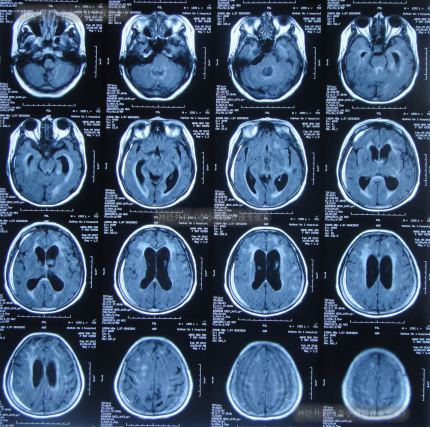

又过2月后即2011年10月14日,夜里2点起夜时突然站不稳,再次出现头昏,呕吐频繁,四肢无力,2011年10月17日第2次就诊于第2家医院:呼和浩特市某医院神经内科住院治疗,行头颅MRI(图-1)认为“末梢神经脱髓鞘病变,考虑为格林巴利综合征,轻度脑积水”。

图-1:2011年11月17日头颅核磁